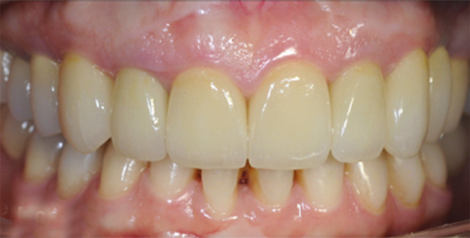

ПОСЛЕ

Проведено лечение брекет-системой, установлены имплантаты в жевательном отделе, изготовлены виниры и безметалловые коронки на зубы в зоне улыбки, восстановлена дикция, устранены морщины в уголках рта.